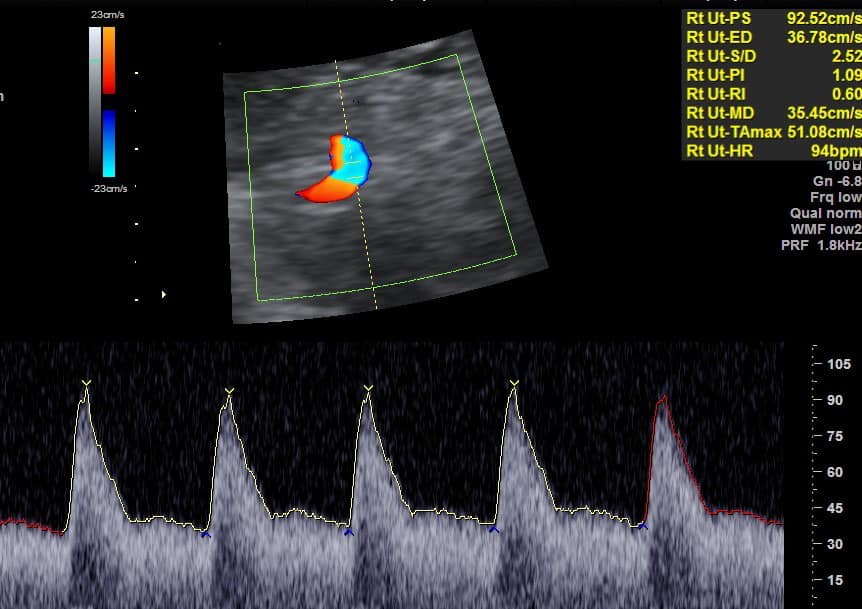

Az első trimeszteri ultrahang során vizsgálható a méhet ellátó anyai erek áramlása, melynek paraméterei felhasználhatók a toxémia szűrésében. Emellett az anyai vérből vett fehérje szintjének vizsgálata is beletartozik. Ez a fehérje a PLGF, mely a lepény kialakulásában játszik fontos szerepet. Alacsony szintje a lepény kóros fejlődésére utal. Mérik az anyai vérnyomásértékeket, mindkét karon többször mérve. A szűrés figyelembe veszi az anyai anamnézist is. Ezeket összekombinálva kapunk egy kockázatot, mely 90 %-os pontosságú, 10 % fals pozitív eredmény mellett. A preeclampsia szűrés a 32 hét előtt megjelenő toxémia kockázatát szűri.

A mellékelt kép a méhet ellátó artéria normál áramlását mutatja az első trimeszteri ultrahang során.